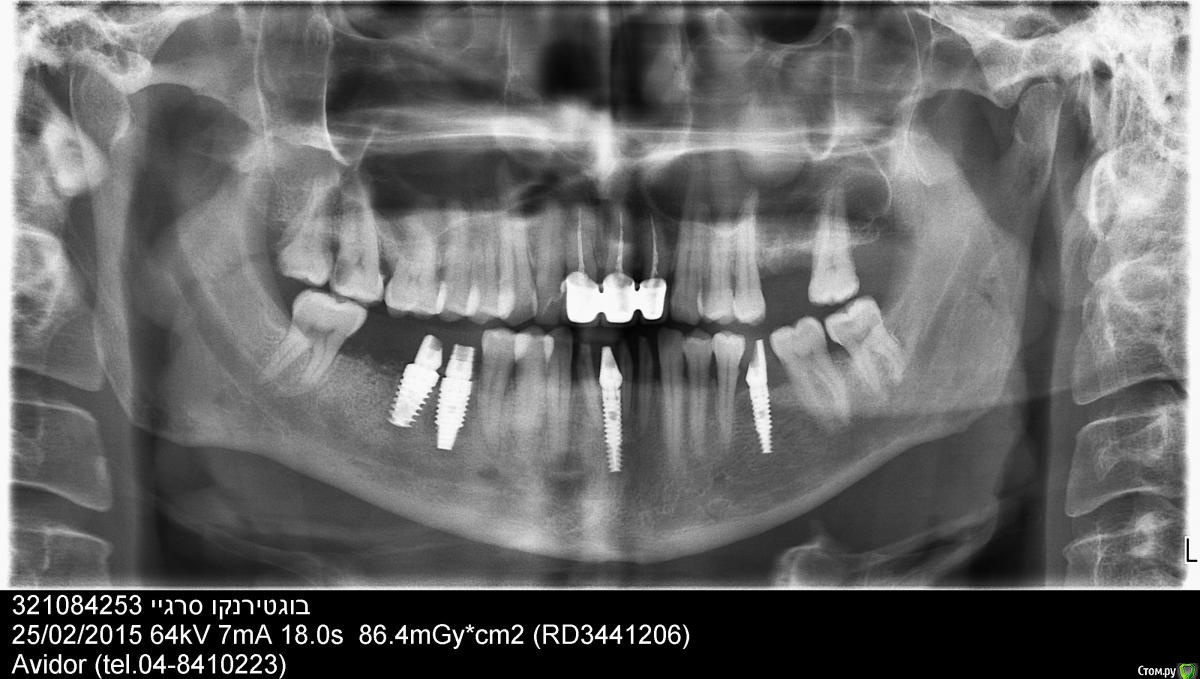

Сергей1971 Опубликовано 25 февраля, 2015 Поделиться Опубликовано 25 февраля, 2015 Доброго времени суток всем.3 месяца назад мне установили 4 имплантата. Установка проводилась за границей. После имплантации начали шататься зубы расположенные рядом с передним имплантом,а один из них 7-ка(если я не ошибаюсь правильности отсчета) покраснел изнутри и начал болеть. Так же занемела щека в области установки двух имплантов. Врач сказал,что онемение пройдет в ближайшее время,а по поводу передних зубов,что это произошло по независящим от него причинам,мол там почти не было кости,хотя до имплантации я с ним разговаривал по поводу установки моста (побаивался делать имплантацию,врач меня отговорил от установки моста,сказав что у меня нормальные здоровые зубы и не стоит их портить). Затем он сказал,что надо обьединить передние зубы вместе с имплантом и что это их укрепит. Удалил нервы,обточил. Но и это еще не все. абатмент стоит не в зубном ряду,а как будто глубже во рту,что абсолютно непонятно для меня,почему? Причем абатмент не закреплен жестко с имплантом,а шатается.Онемение тоже еще не прошло,хотя уже не так сильно беспокоит. Врач утверждает,что все правильно и настаивает на установке коронок. Решил написать вам и попросить совета в данной ситуации. Просто у меня такое чувство,что что то совсем не так,как рассказывает мне врач.Особенно после посещения вашего форума... Слишком много непонятного. Решил сделать панораму и КТ. Прилагаю КТ сделанную до имплантации и панораму сделанную после. КТ сделанная после имплантации еще не готова,но если понадобиться,я приложу после. Надеюсь на вашу помощь. https://cloud.mail.ru/public/4f5919b66379/Patient%20name_%20%D7%91%D7%95%D7%92%D7%98%D7%A8%D7%99%D7%A0%D7%A7%D7%95%20%D7%A1%D7%A8%D7%92%D7%99%20321084253%20-MAN.pdf Ссылка на комментарий

Фарид Расулыч Опубликовано 26 февраля, 2015 Поделиться Опубликовано 26 февраля, 2015 Весьма "интересный" выбор позиций имплантов Ссылка на комментарий

Bier Опубликовано 28 февраля, 2015 Поделиться Опубликовано 28 февраля, 2015 В переднем отделе недосажен абатмент, вот по этому он и болтается, вообще конечно с учетом того что зубы депульпировали (хотя на снимке этого не видно), имплантат там вообще был не нужен.Справа имплантаты слишком близко друг к другу, дальний должен был стоять еще дальше. Грубо говоря у вас 2 имплантата на месте 6го зуба и ни одного на месте 7го. 1 Ссылка на комментарий